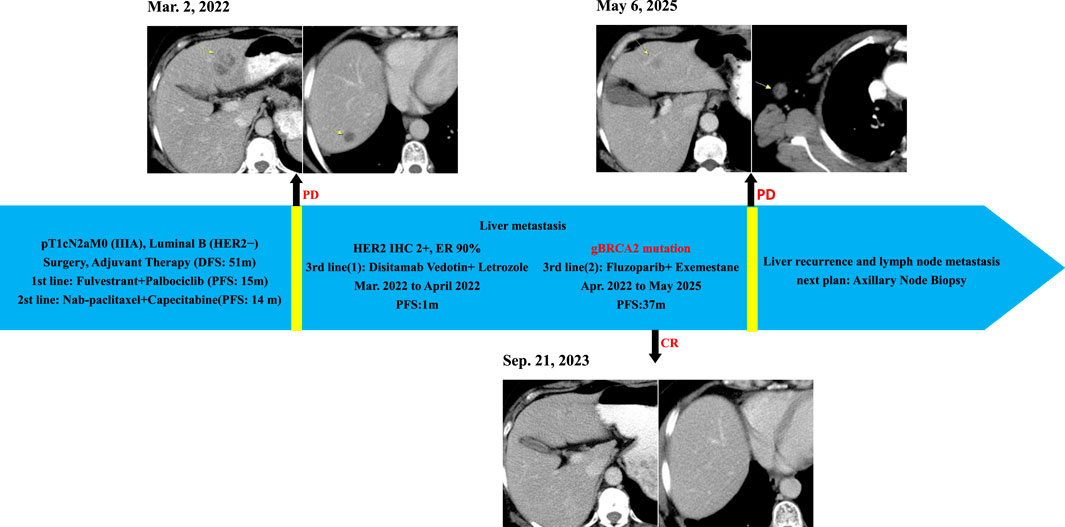

In Feb. 2022, abdominal CT suggested multiple liver metastases (Figure 1). Subsequently, the patient presented to our hospital. Ultrasound-guided biopsy confirmed metastatic breast cancer (IHC: ER 90%, PR 1%, HER2 IHC 2+) (Figure 2). FISH for HER2 was negative. Due to HER2 IHC 2+, Disitamab Vedotin was initiated as third-line therapy (March 2022-April 2022). Concurrently, Letrozole was added based on high ER expression. After two cycles, CT showed minimal response.

Figure 1

Timeline of medical imaging showing cancer progression and treatments. Top-left, images from March 2, 2022, show initial tumor. Top-right, May 6, 2025, indicates progression. Bottom images, September 21, 2023, display further changes. Blue arrow highlights treatment timeline with text detailing cancer type, treatments, and duration. Mentioned interventions include Fulvestrant, Palbociclib, Nab-paclitaxel, Capecitabine, Disitamab Vedotin, Letrozole, Fluzoparib, and Exemestane. Notes indicate disease progression (PD) and complete response (CR). Upcoming plan outlines axillary node biopsy.

Figure 1. Clinical Course and Imaging Surveillance Timeline. 1) Contrast-enhanced CT (Mar. 2, 2022) showed multiple enhancing lesions consistent with hepatic metastases; 2) Contrast-enhanced CT (Sep. 21, 2023) demonstrated no evidence of hepatic metastasis; 3)Contrast-enhanced CT (6 May 2025) showed suspected recurrent metastatic lesion in the left hepatic lobe and metastatically enlarged right axillary lymph node.

In Apr. 2022, blood-based NGS detected a pathogenic gBRCA2 exon 11 variant (c.6462_6463del; p.Q2157Ifs*18; VAF 49.7%), confirming HRR deficiency. Based on this molecular evidence combined with persistent high ER expression—and considering the patient’s preference for oral therapy and economic factors favoring domestically developed agents—treatment was transitioned to oral Fluzoparib (300 mg twice daily) plus Exemestane (25 mg daily) in Apr. 2022.

Results of molecularly guided therapy

Follow-up imaging (CT) demonstrated complete resolution of the previously identified liver metastases (Figure 1). The patient achieved a PFS of 37 months on Fluzoparib plus Exemestane. This duration represents the longest period of disease control in her metastatic course. Treatment was well-tolerated. Adverse events included: anemia (CTCAE Grade 2, managed with intermittent Erythropoietin), nausea (CTCAE Grade 1, managed with Ondansetron prn), and rash (CTCAE Grade 1, managed with topical steroids). No dose reductions or treatment interruptions were required.

Disease progression occurred in May 2025, evidenced by a new right axillary lymph node metastas and possible recurrence in the left liver lobe on CT (Figure 1), meeting RECIST 1.1 criteria. Planned evaluations include liver MRI, biopsy of the axillary node for IHC (ER, PR, CerbB2, PD-L1, MMR, TROP2) and genetic analysis (BRCA1/2 reversion, HER2, PIK3CA, ESR1) to guide next-line precision therapy.